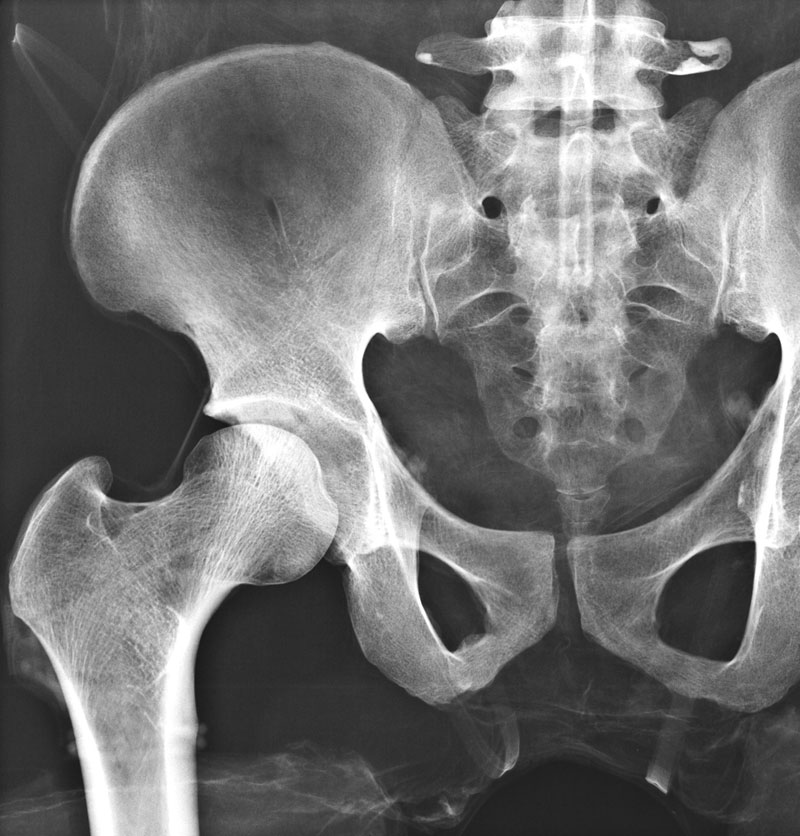

Röntgenphantom Hüfte, transparent

Unsere weltweit einmaligen Röntgenphantome enthalten echte menschliche Skelett - Teile. Dies gewährleistet erstklassige Aufnahmen und realistische Übungsbedingungen. Eine praxisnahe Röntgen - Ausbildung ist ohne diese Modelle nicht möglich. Jedes Modell wird in handwerklicher Einzelstückfertigung hergestellt und ist jeweils ein Unikat. Bedingt durch die Verwendung von echten Knochen und die individuelle Fertigung weichen die einzelnen Modelle in Größe und Beschaffenheit voneinander ab. Ausführung transparent! Abbildung zeigt Modell 7245, Opak-Ausführung!

7240

7.016,81 € (8350,00 €)

7245

Röntgenphantom Hüfte, Opak

6.949,58 € (8270,00 €)